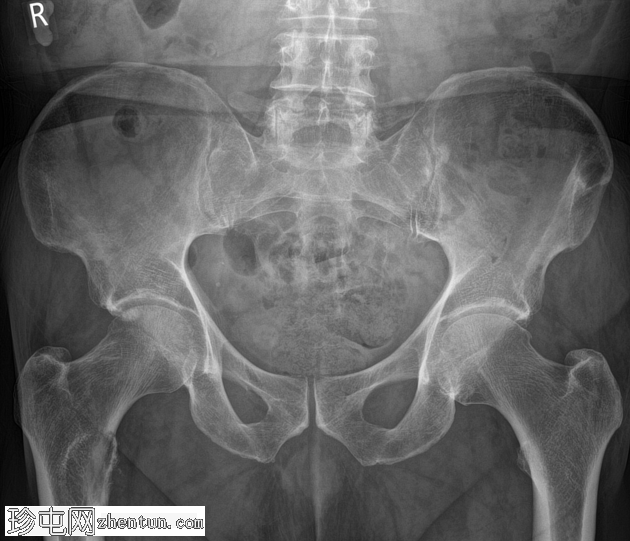

右髋部疼痛加剧,负重困难。已知甲状腺癌骨转移。

右股骨近端小转子水平处出现溶骨性病变,病变呈扩张性,并伴有皮质破坏。鉴于已知甲状腺恶性肿瘤伴骨转移病史,推测为转移性病变。无病理性骨折。

建议骨科/肿瘤科诊治。